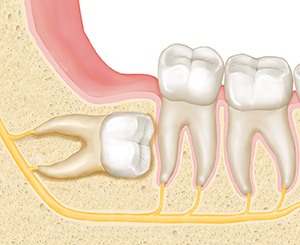

Wisdom teeth that can’t fully break through the gum (erupt) are called impacted. These teeth can grow in almost any direction, including:

Straight up, but without room to erupt into a healthy position

Angled away from the other teeth

Parallel to the gumline

Angled in toward the other teeth

| Straight upward. |

| Parallel to the gumline. |